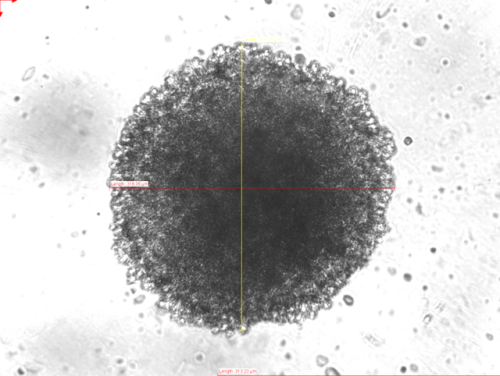

In addition to performing chemical syntheses of new molecules in the wet lab, our group also runs a cell culture lab. Here, we perform first investigations on the biological activity of our new metal complexes and bioconjugates. We carry out cytotoxicit and viability assays, study metabolism and cell death mechanisms, and investigate compound localization intra-cellularly by fluorescence microscopy. More recently, we have expanded the traditional "2D" cell culture (where cells are grown and studied as monolayers in flat-bottom plates) to 3D cell culture, where cancer cells grow in three dimensions, so-called "spheroids". In comparison to monolayer cell cultures, these multi-cellular tumour spheroids (MCTS) are able to accurately simulate many features of in vivo human solid tumours, such as their spatial architecture, physiological responses, secretion of soluble mediators to facilitate inter-cellular communicaton, gene expression patterns, and drug resistance mechanisms.

We study the anti-proliferative activity of synthesized compounds in 2D cell culture and solid 3D tumor spheroids, and we develop metal-based imaging dyes so as to detect intracellular localization of metal complexes and metabolic activity. More advanced biomedical experiments and techniques are carried out with our collaborators in the Medical Faculty at RUB, and elsewhere. In collaboration, we also use confocal microscopy and advanced techniques like lifetime imaging (FLIMS).